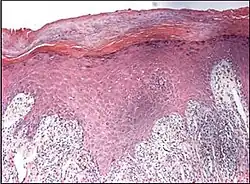

Generally/Not otherwise specified Typical findings:[2]

• In the papillary dermis: a confluent, band-like, dense inflammation of mainly small lymphocytes and a few histiocytes, along or hugging the dermoepidermal junction.

• Often vacuolar degeneration of basal keratinocytes and apoptotic bodies (colloid or Civatte bodies).